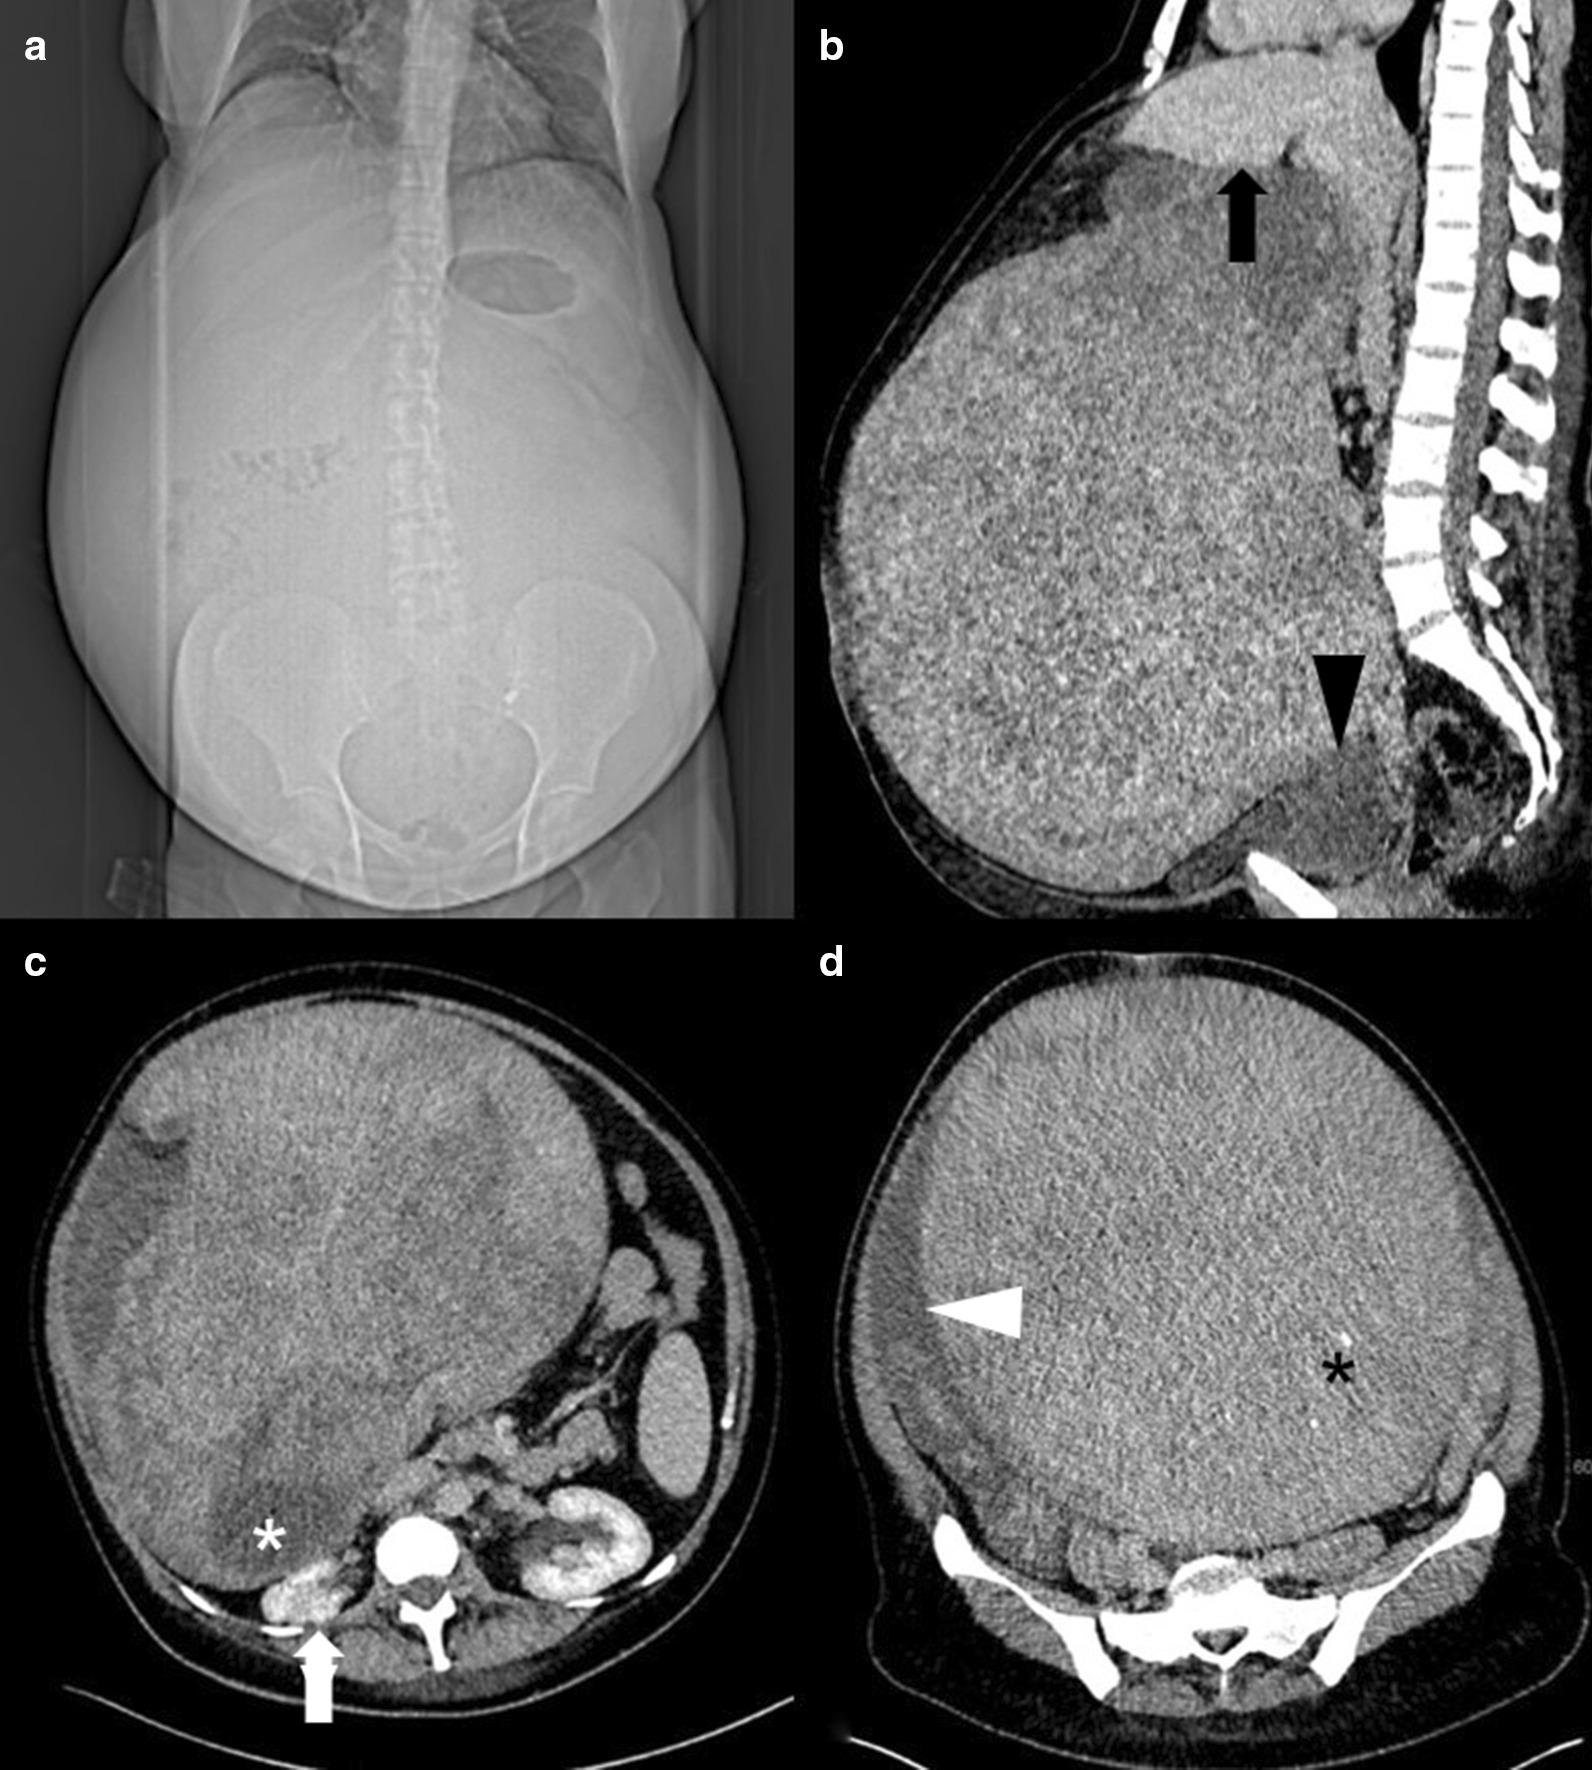

In our clinic, a preliminary physical examination was performed, which indicated good general condition and no evidence of pallor or pedal edema. The patient’s preoperative body mass index (BMI) was 32.1 kg/m2. Her abdomen was enormously enlarged and pendulous with flank fullness on both sides. An irregular mass arose from the pelvis up to the xiphisternum and was not discernible owing to abdominal wall obesity. There were no hernias or abdominal varices. Renal angle fullness was not observed. Because of the patient’s anxiety, a vaginal examination could not be performed. Transabdominal ultrasound showed a huge intraabdominal mass. The right kidney showed impaired cirrhosis, while the left kidney showed compensatory enlargement. A small amount of ascites was observed. An urgent computed tomography (CT) scan was performed revealing a large tumor that occupied the abdominopelvic cavity completely. On the CT scan, the mass measured 32 × 27 × 34 cm (intralesion diameter) and could not be visibly separated from the uterine cavity, bladder, or liver (Fig. 1). The tissue of origin and extent of tumor invasion remained unclear. The mass appeared heterogeneous, containing cystic and necrotic areas along with solid components. It compressed the intestines, right kidney, and both ureters. The spleen was mildly enlarged. The hepatorenal recess (Morison’s pouch) showed minimal ascites. No lymph nodes were observed. Due to the slow growth of the tumor, few ascites, and negative lymph nodes, malignancy was highly unlikely.

Fig. 1.

CT reveals extensive abdominal enlargement in the scout view (a). Sagittal CT reconstruction depicts a giant tumor in contact with the liver (black arrow, b) and with the urinary bladder (black arrowhead, b). The mass contains necrotic components (white asterisk, c), as well as small calcifications (black asterisk, d). The preoperative situs shows compression of the right kidney (white arrow, c) and ascites adjacent to the tumor (white arrowhead, d)